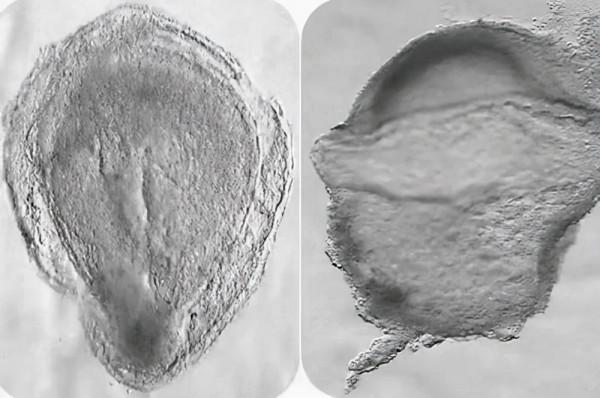

圖片來源:Srinivas, Scialdone

英國牛津大學的Shankar Srinivas和同事分析了一個在自願終止妊娠後被捐贈用於研究的人類胚胎,該胚胎所處的階段相當於受精後的第16至19天。

研究人員對胚胎中的細胞型別和這些細胞表達的基因進行了詳細的描述,並與實驗模型進行了對比。研究人員最終檢測到了原始生殖細胞(成為卵子或精子細胞的幹細胞)和紅細胞等等。